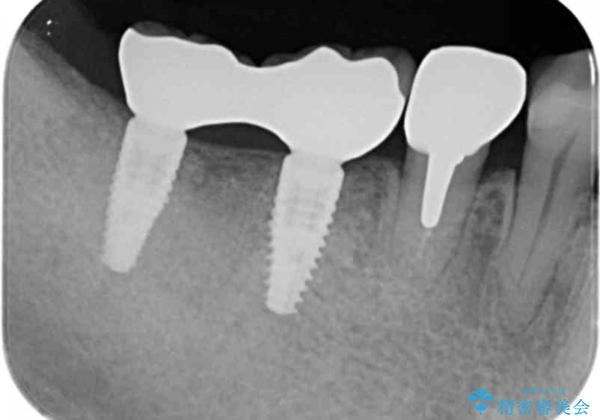

ブリッジを支える歯が割れてしまい、抜歯が必要であることと、骨の大きな吸収が見られました。

インプラント治療を行うにあたり周囲に骨を造成することで安定して噛める環境の整備を計画します。

今回はインプラント埋入時に固定が得られたので同時に骨の造成を行い治療を進めることができました。